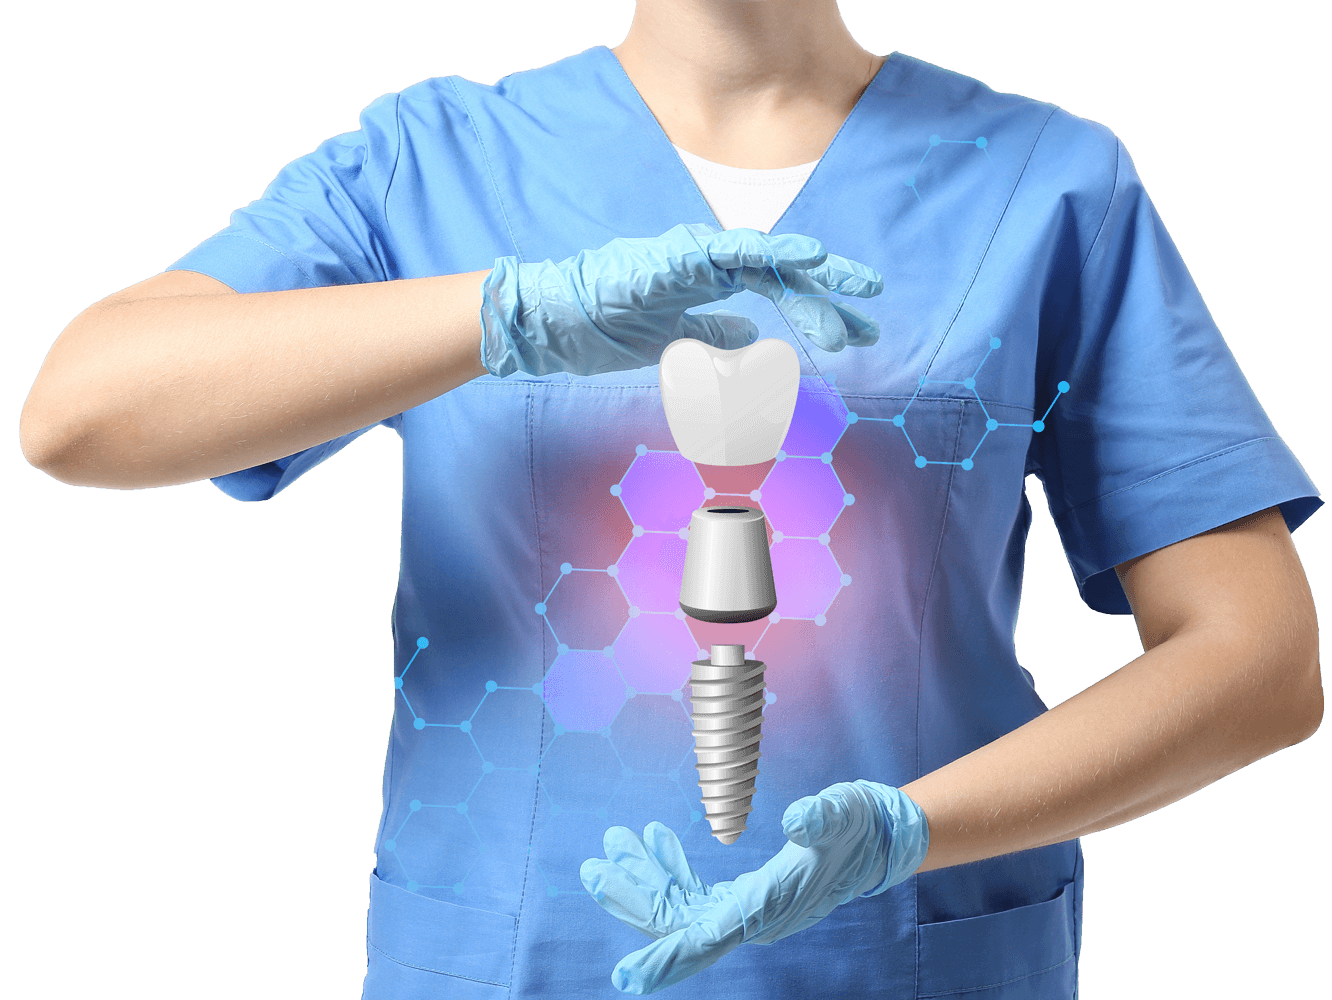

Dental crowns are fixed restorations designed to fully cover a damaged or weakened tooth, or a dental implant, restoring its original shape, size, strength, and function. They also provide a significant improvement to the appearance of your smile. This is an ideal solution for patients looking to regain chewing ability and natural-looking teeth.

A dental crown is a tooth-shaped “cap” placed over a natural tooth or implant. It’s used to protect the underlying structure, restore function, and improve appearance.

- Completes implant treatments by serving as the visible tooth